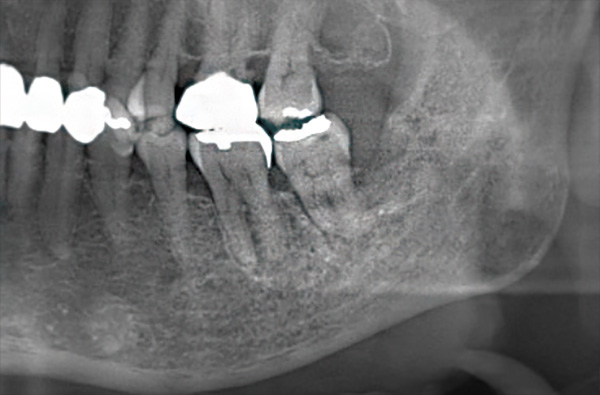

右下小臼歯の後方に骨露出と排膿あり。

肉眼的露出は軽度だが、パノラマ写真では広範囲の骨吸収と腐骨形成(矢印)が確認されます。